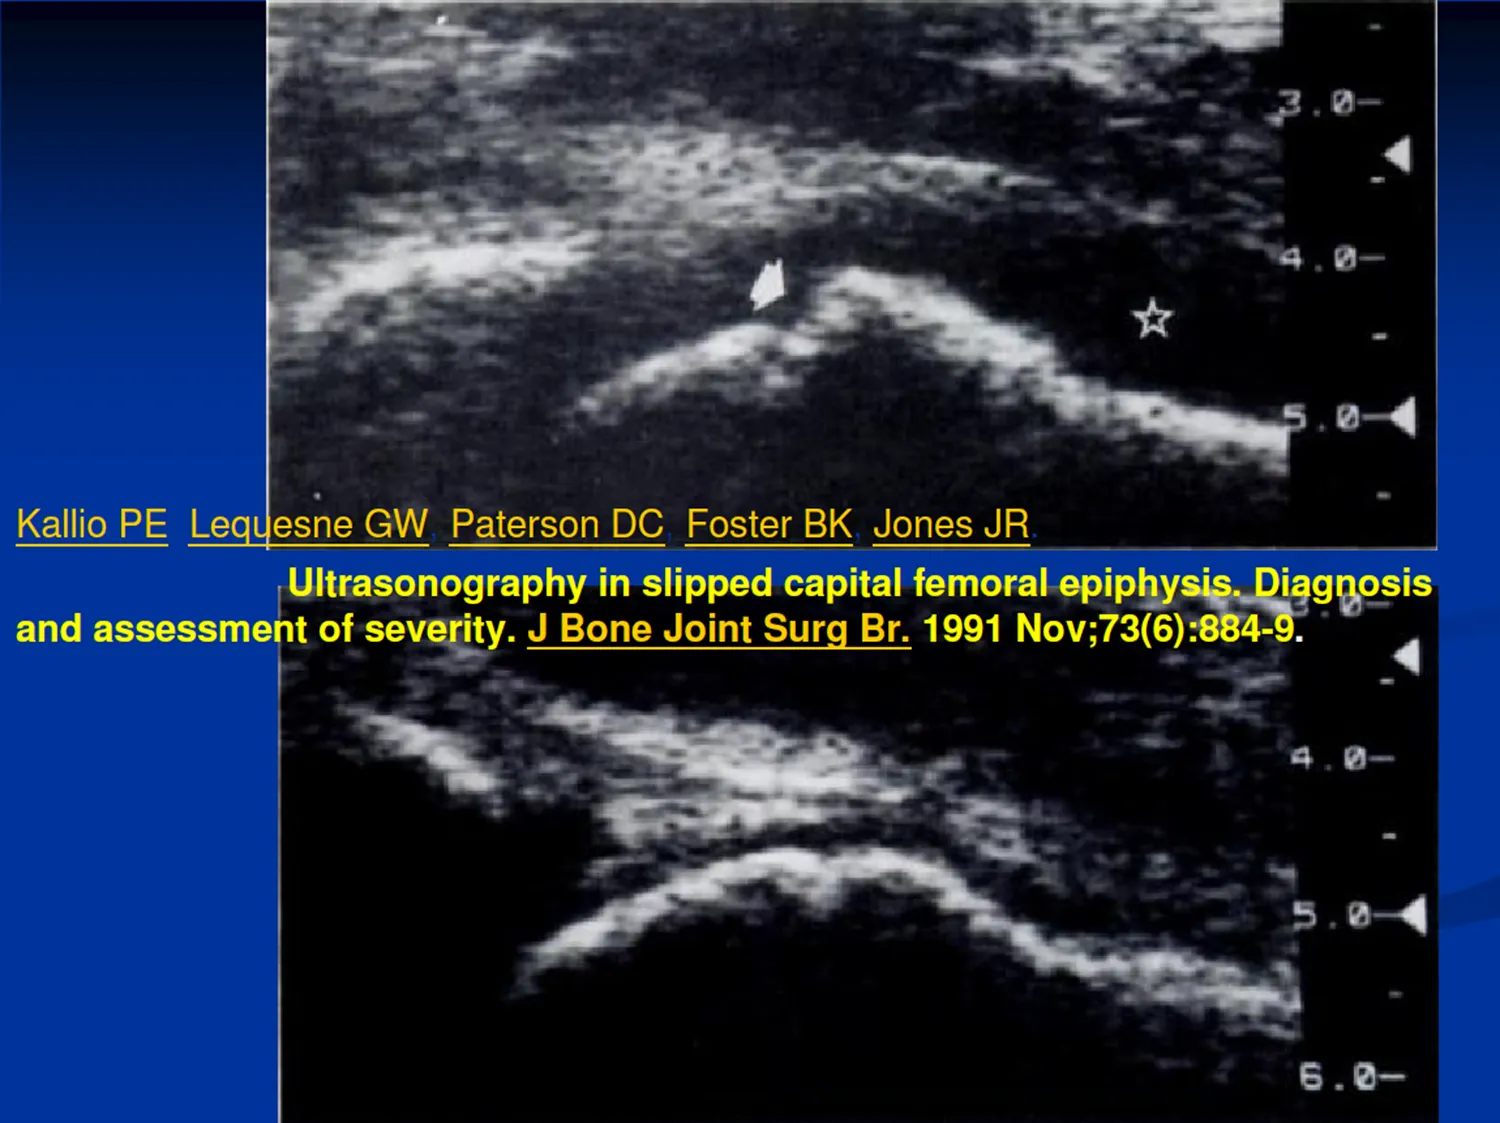

F. Slipped capital femoral epiphysis (SCFE)

(1) Ultrasound : step at the ant. physeal line

J Bone Joint Surg Br. 1991 Nov;73(6):884-9